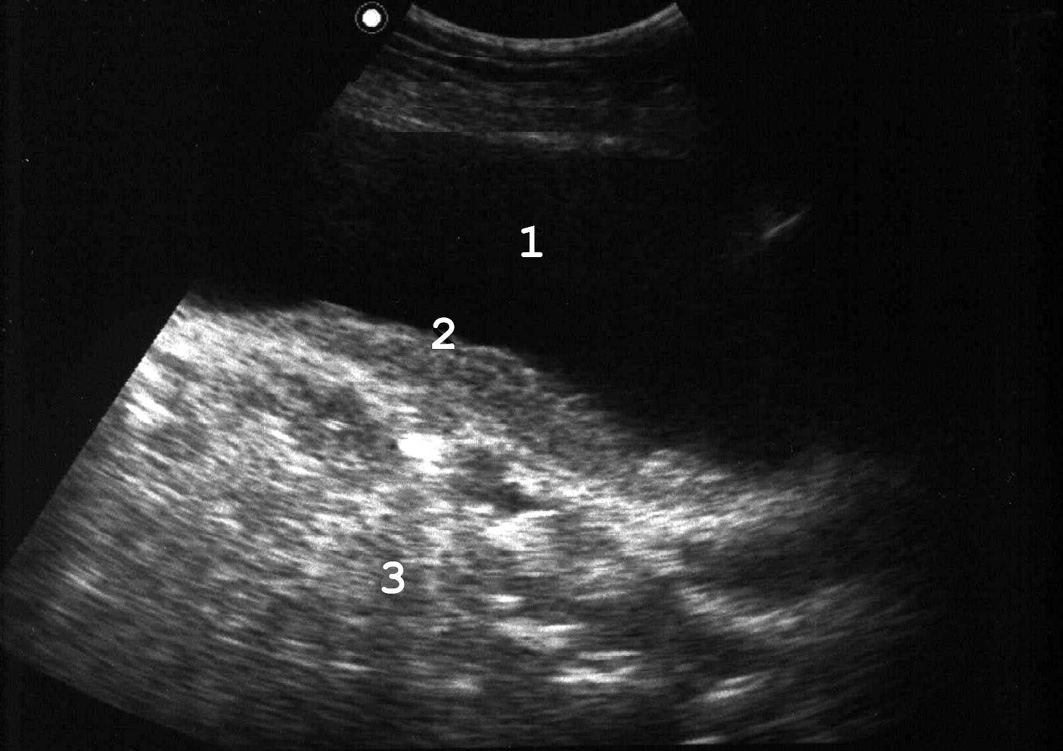

Рис. 4. Сонограмма мочевого пузыря в норме: 1 − мочевой пузырь; 2 − простата; 3 − стенка мочевого пузыря нормальной структуры и толщины. (Продольное сканирование, конвексный датчик 5 МГц, “Logiq-500”).

Рис. 5. При хронической задержке мочи вначале развивается гипертрофия мышечной оболочки мочевого пузыря: 1 − мочевой пузырь; 2 − увеличенная простата; 3 − утолщенная стенка мочевого пузыря. (Продольное сканирование, конвексный датчик 5 МГц, “Logiq-500”).

Рис. 6. В дальнейшем появляется трабекулярность его стенок: 1 − мочевой пузырь; 2 − простата; 3 − стенка пузыря утолщена, с выраженной трабекулярностью. (Продольное сканирование, конвексный датчик 5 МГц, “Logiq-500”).

Рис. 7. В конечной стадии происходит перерастяжение стенок мочевого пузыря: 1 − мочевой пузырь; 2 − простата; 3 − истонченая трабекулярная стенка. (Продольное сканирование, конвексный датчик 5 МГц, “Logiq-500”).

Наиболее часто гипертрофия стенок связана с нарушением оттока мочи вследствие инфравезикальной обструкции. Ее причинами могут быть доброкачественная гиперплазия или рак предстательной железы, функциональный или органический стеноз шейки мочевого пузыря (болезнь Мариона), стриктура уретры. При прогрессировании заболевания и увеличении объема остаточной мочи утолщение мышечных пучков становится неравномерным, внутренняя поверхность мочевого пузыря принимает трабекулярный вид (рис. 6). Длительное существование хронической задержки мочи приводит к дальнейшему истончению стенок пузыря (рис. 7). Объем остаточной мочи может при этом достигать 1 л и более.